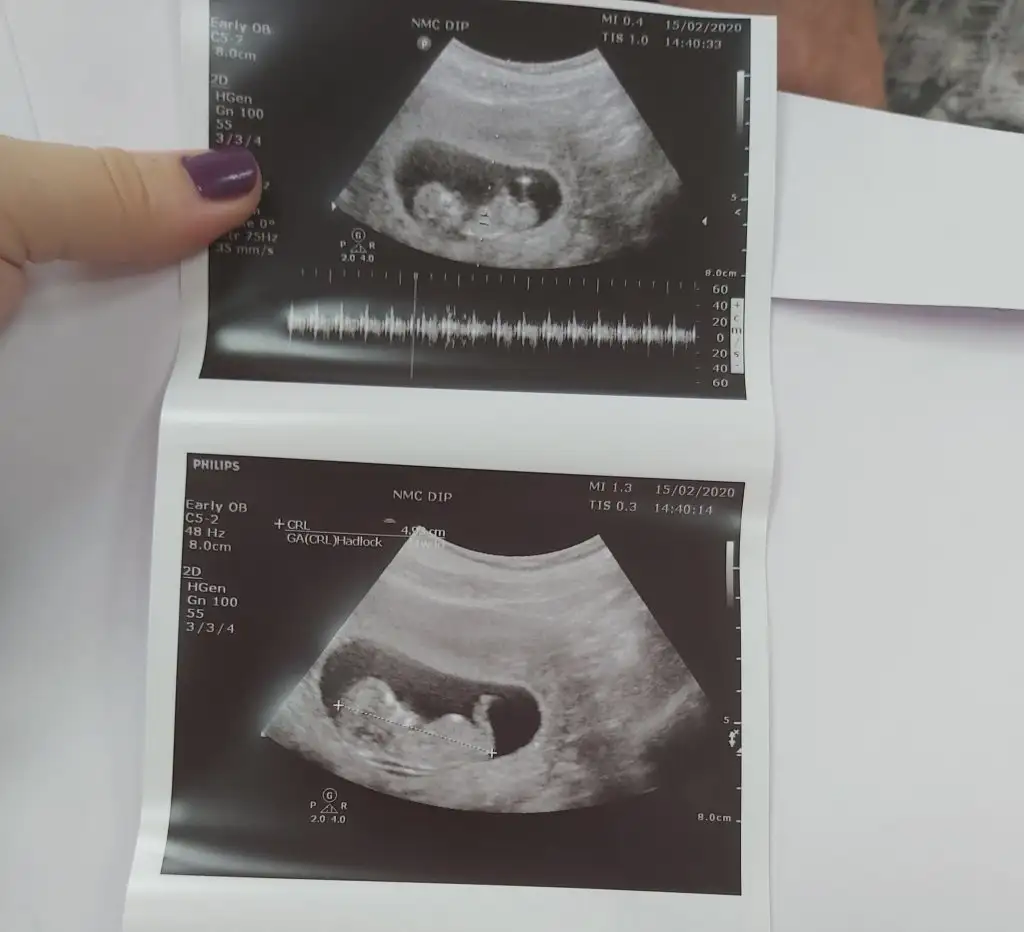

Ben burayı nasıl kaçırmışım.En son ultrason resmimiz 11+3 'ten.Tahmin alabilir miyim arkadaslar🙏

• 20200215_142051.webp

20200215_142051.webp

26,1 KB · Görüntüleme: 65